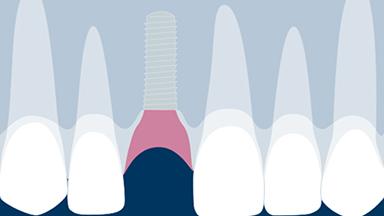

种植体支持式临时修复体

当为患者提供种植体支持式修复时,临床医生必须决定是制作临时修复体还是直接戴入最终修复体。有几个因素对做出正确的决定很重要。这些因素包括前牙区或后牙区种植部位、种植体的数量,是否需要对组织塑形(常见于前牙区的相邻种植体),以及是否需要咬合支持。患者的期望也可能在此决定中发挥作用。本模块将重点介绍种植体支持式临时修复体的适应症,以及制作材料和使用的技术。